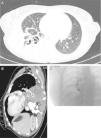

(A) Chest CT with contrast medium (parenchymal window), showing a lung abscess associated with necrotizing pneumonia of the right lower lobe. (B) Sagittal chest CT slice (mediastinal window), showing a mycotic aneurysm in the infero-medial segmental branch (asterisk). (C) Pulmonary arteriography performed before embolization of the aneurysm.

We report the case of a 29-year-old woman, smoker of 10 pack-years, with recent onset of diabetes mellitus type 1 (ketoacidosis the week before presentation of this clinical episode). She consulted due to a few hours history of dyspnea, fever 38°C, pain in the right flank, cough and rust-colored expectoration. Auscultation revealed crackles in the right lung base. Clinical laboratory tests showed significant leukocytosis (30100/μl) and elevated CRP (224mg/l). Consolidation of the right lower lobe was observed on chest radiograph. The patient was diagnosed with community-acquired pneumonia, and empirical antibiotic therapy was started. The chest computed tomography (CT) scan showed consolidation of the pulmonary parenchyma in the right lower lobe, with the formation of a thick-walled hypodense lesion containing air bubbles, with axial diameters measuring 6.1cm×4.2cm, consistent with an abscess (Fig. 1A). During hospitalization in the general ward, the patient had several episodes of hemoptysis, so fiberoptic bronchoscopy was performed, revealing total stenosis of the right anterior basal bronchus (B8) and partial stenosis of the right basal-lateral bronchus (B9) with necrotic tissue on solid tissue. Given the lack of clinical improvement, the chest CT was repeated, showing, in addition to the necrotizing consolidation, aneurysmal dilation of the exit of the segmental artery of right bronchial segment 10, consistent with mycotic aneurysm, measuring 1.4cm in length and 5cm in diameter (Fig. 1B). Arteriography (Fig. 1C) confirmed the diagnosis. The aneurysm was successfully embolized with a 14-mm type 2 Amplatzer® plug and hemoptysis was controlled. The source of the aneurysm and the right lower truncal branch were subsequently embolized with 10-mm coils and an 8-mm Amplatzer® plug. Bronchial biopsy obtained during the bronchoscopy showed the presence of hyphae consistent with mucormycosis, so treatment began with liposomal amphotericin and caspofungin. Following this, the patient showed slow but clear clinical improvement. Lower right lobectomy was performed by posterolateral thoracotomy, revealing pleural adhesions throughout the lung surface, particularly between the lower right lobe and the diaphragm. The postoperative period was free of complications, recovery was favorable, and cure was achieved.